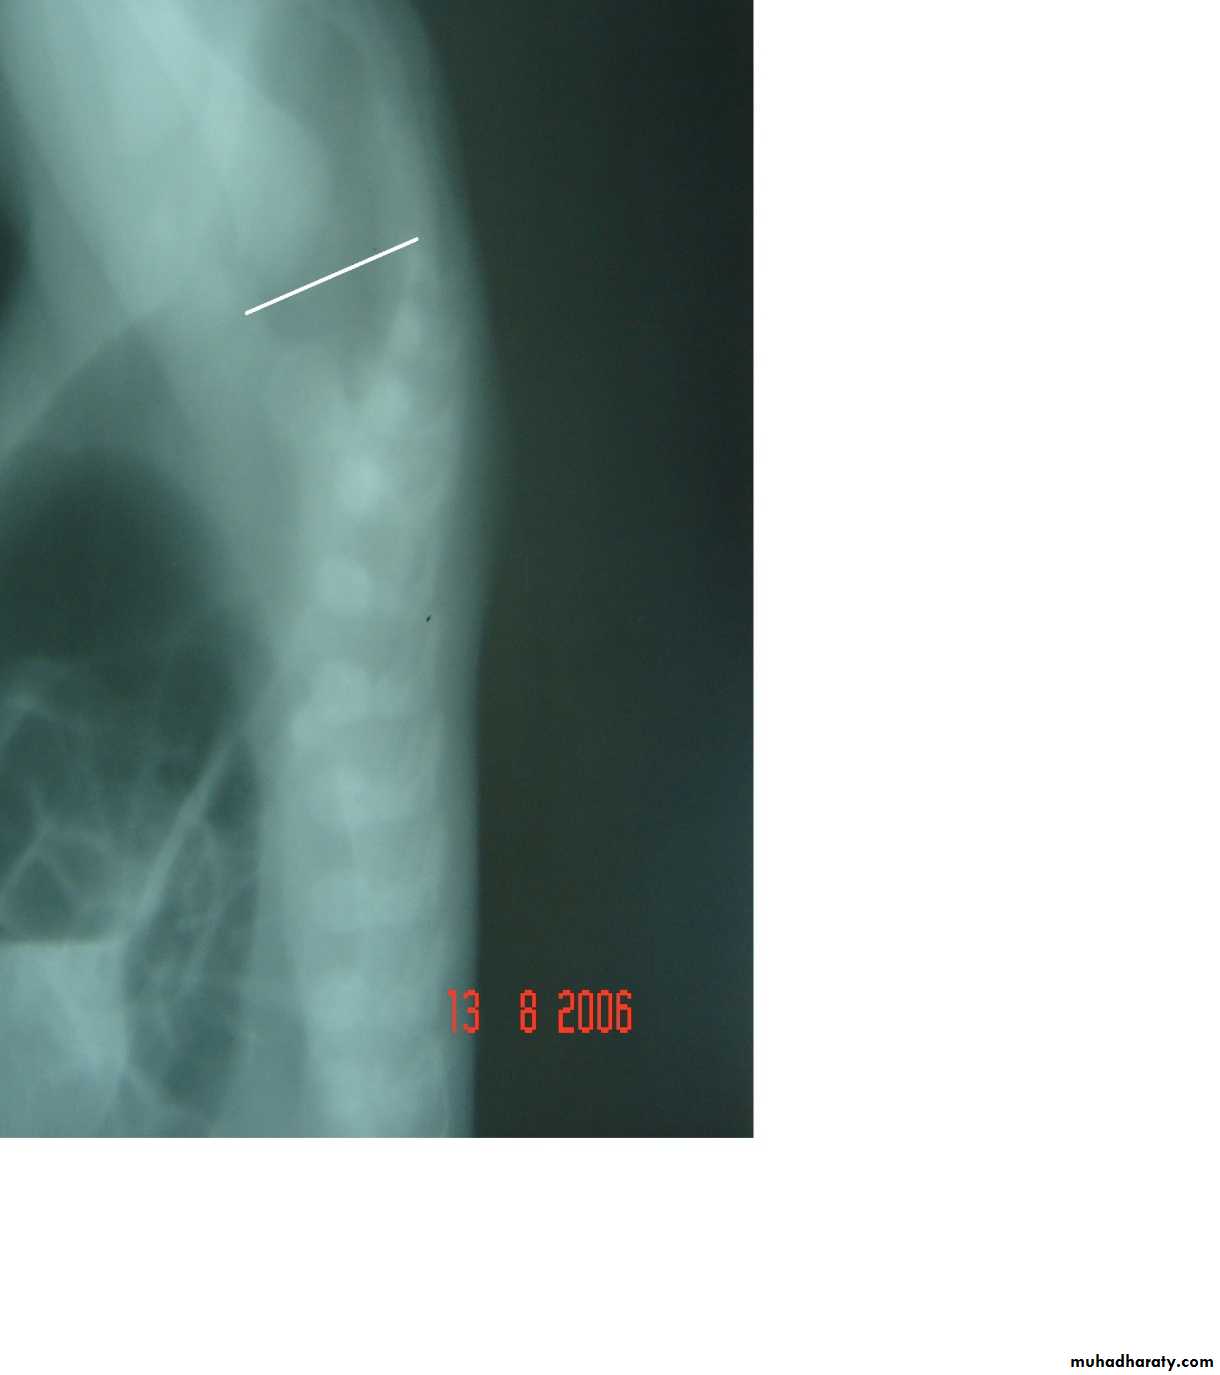

Respiratory Distress in the NewbornFirst photo:

Diagnosis: eventration of diaphragmDescription: mild dextrocardia – recurrent chest infection – diaphragm is present

mild distress - 7 months age baby – less number of intestinal loops in the chest

there is lung tissue in the chest - Paradoxical movement of the diaphragm.

Treatment: plication of the hemi-diaphragm (through thoracic approach).